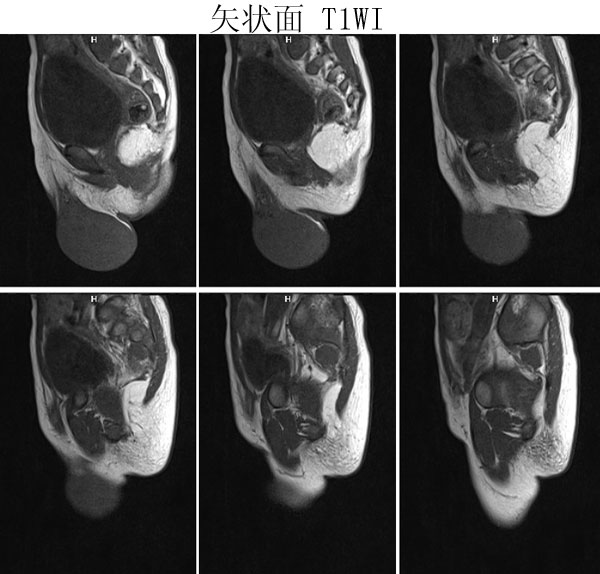

(广东同江医院的病例)男,2岁。左侧睾丸肿大3月,开始发现时红枣大,逐渐增大,现鸡蛋大小,表面光滑,无压痛,质地中等。

病理诊断 :(左侧)

睾丸胚胎性横纹肌肉瘤

,瘤组织局部浸润附睾组织,精索残端组织内未见瘤组织浸润。